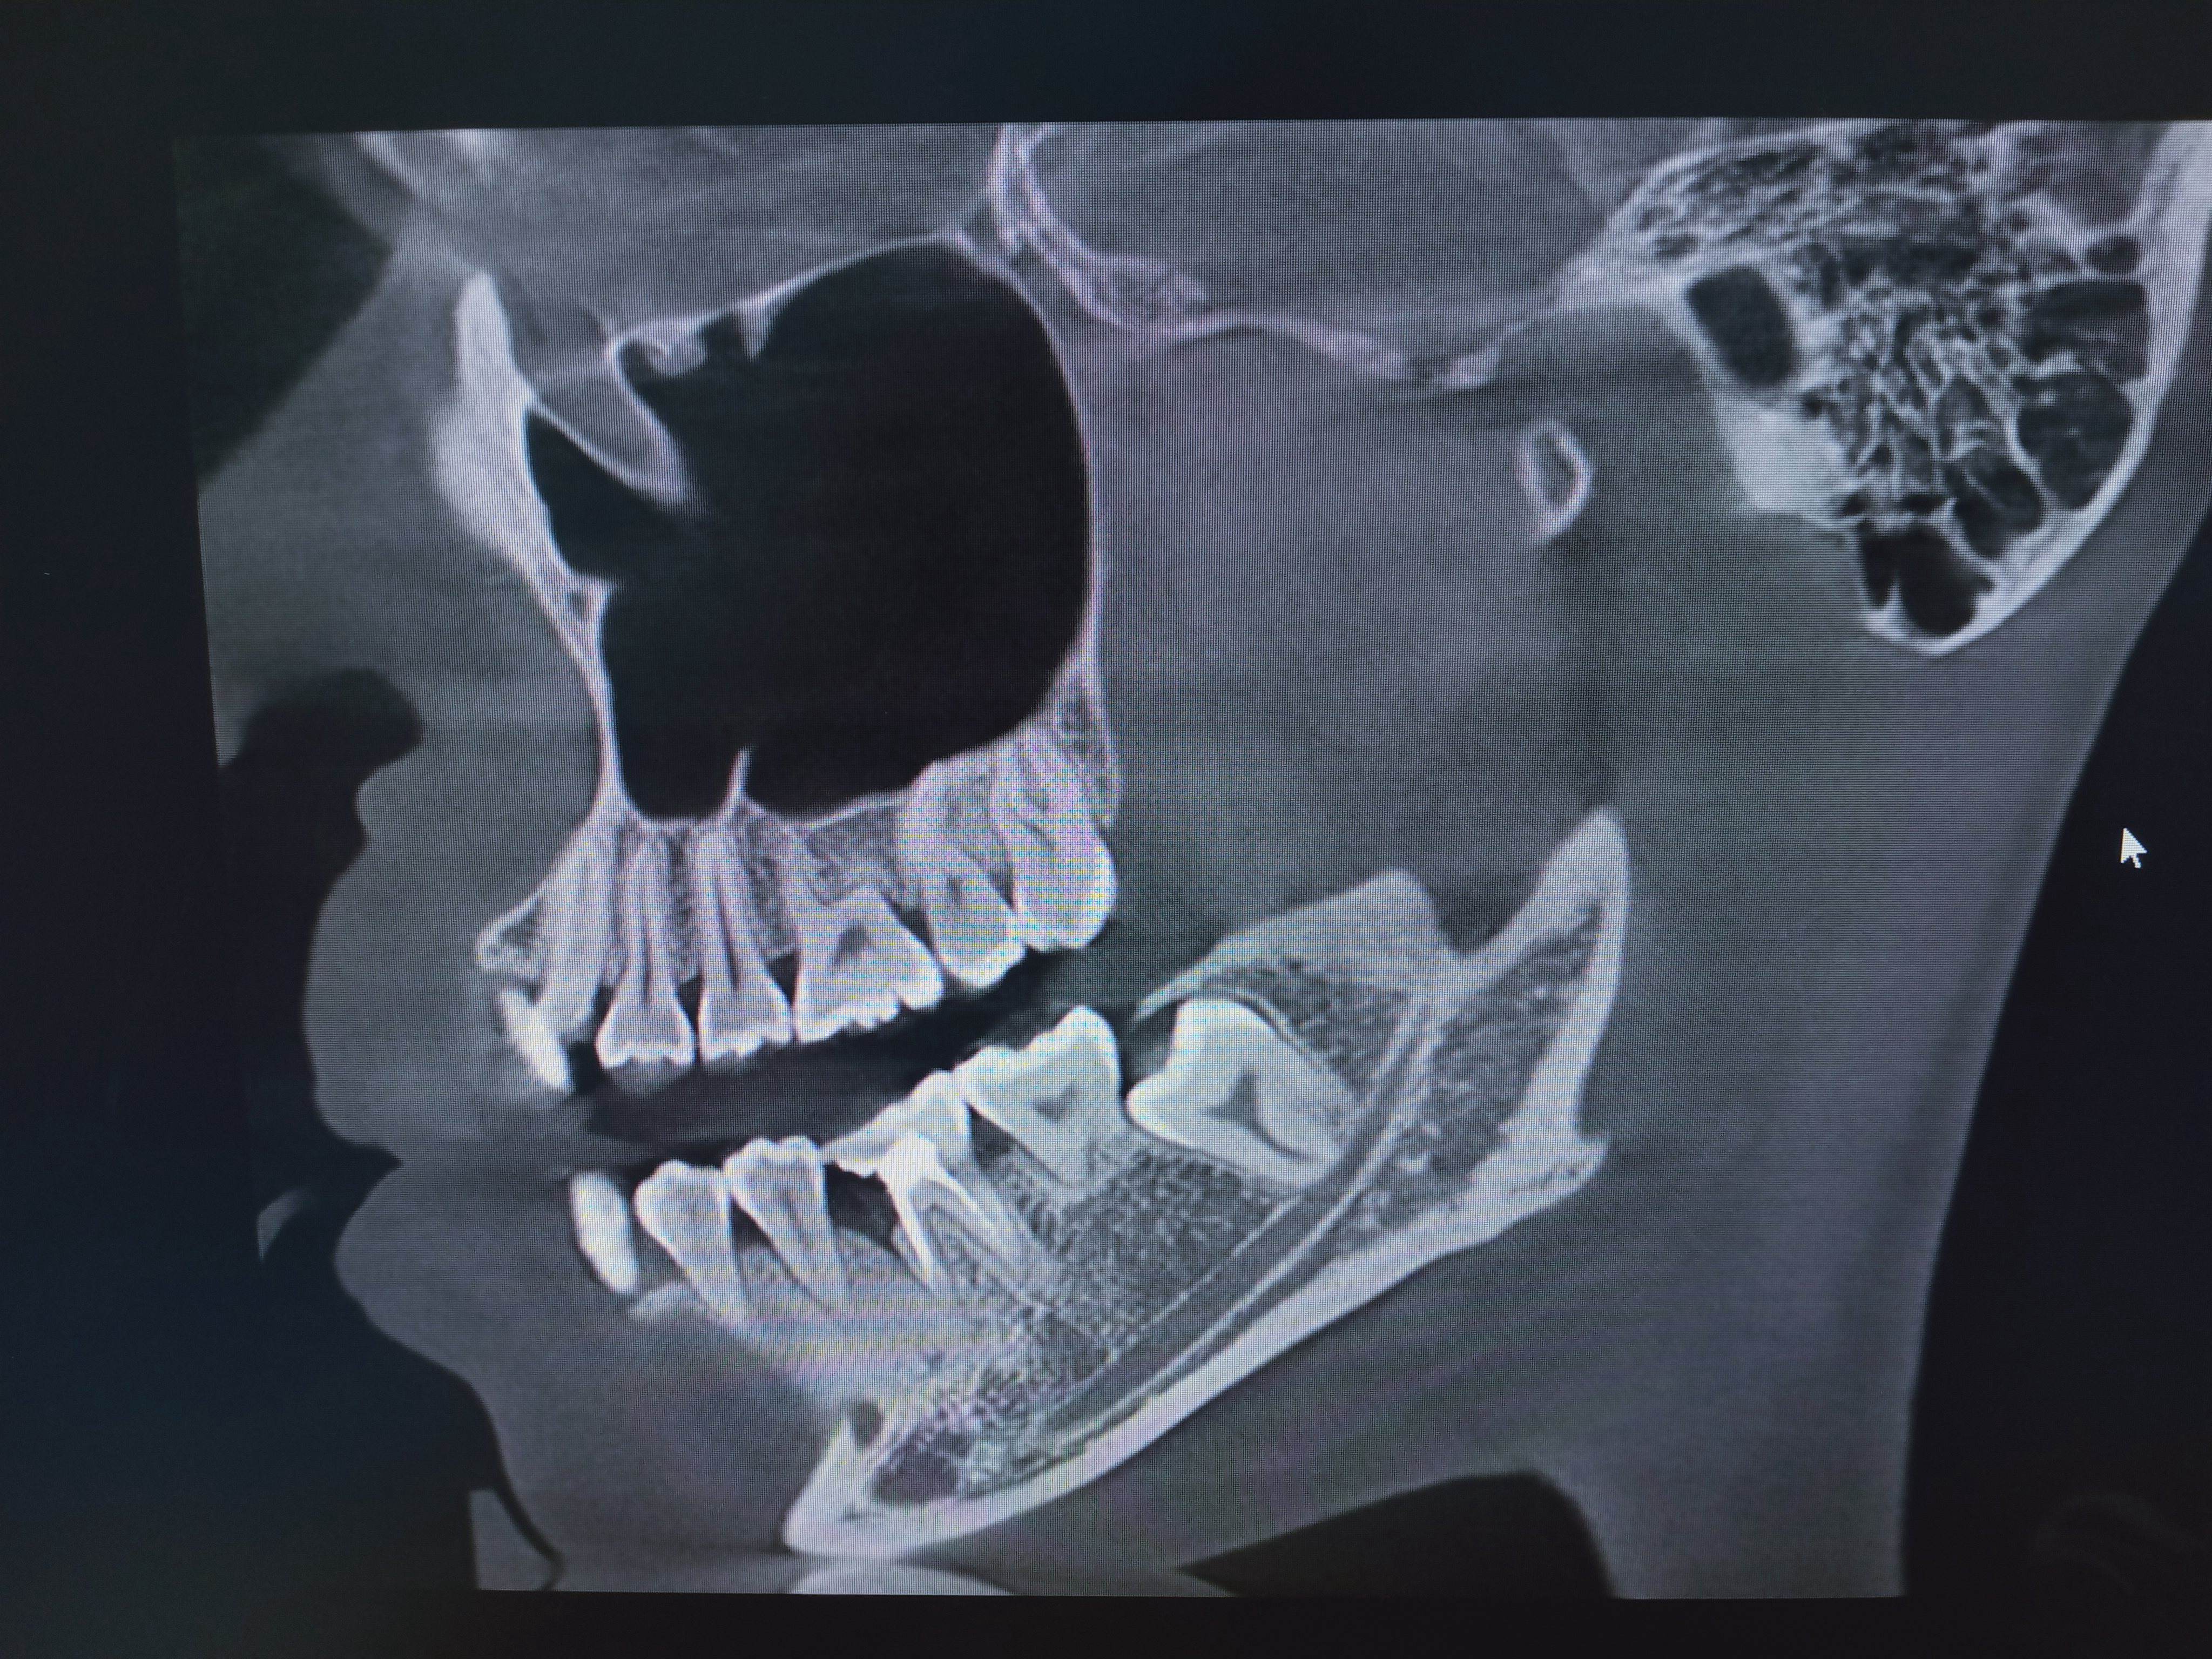

2、口腔CT(锥形束CT):可从三维角度对组织情况进行反映,准确清晰地诊查各组织的健康状态,病损范围及与周围组织间的关系以及发现更加细微的病变,诊查各类阻生牙的位置状态及与临近的神经和窦腔的位置距离,协助医师们在进行术前方案设计以及术后科学评价,还可清晰地检查牙槽骨内的病损。